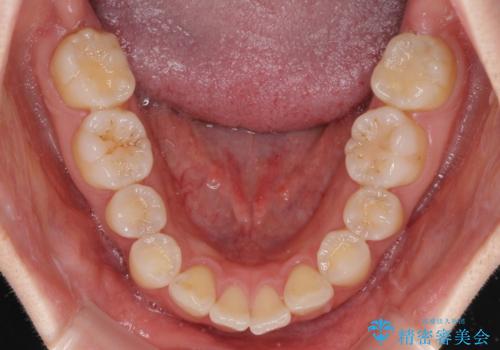

- 上顎前歯の突出感を気にして来院された患者様です。

下顎前歯2本が先天欠損しており、上顎歯列に対して、下顎歯列がアンバランスに小さい状況でした。

左右上顎側切歯2本が矮小歯であるため、上顎の抜歯ではなく、IPR(歯と歯の間を削る)と歯列全体の後方移動によってバランスを整えることとしました。